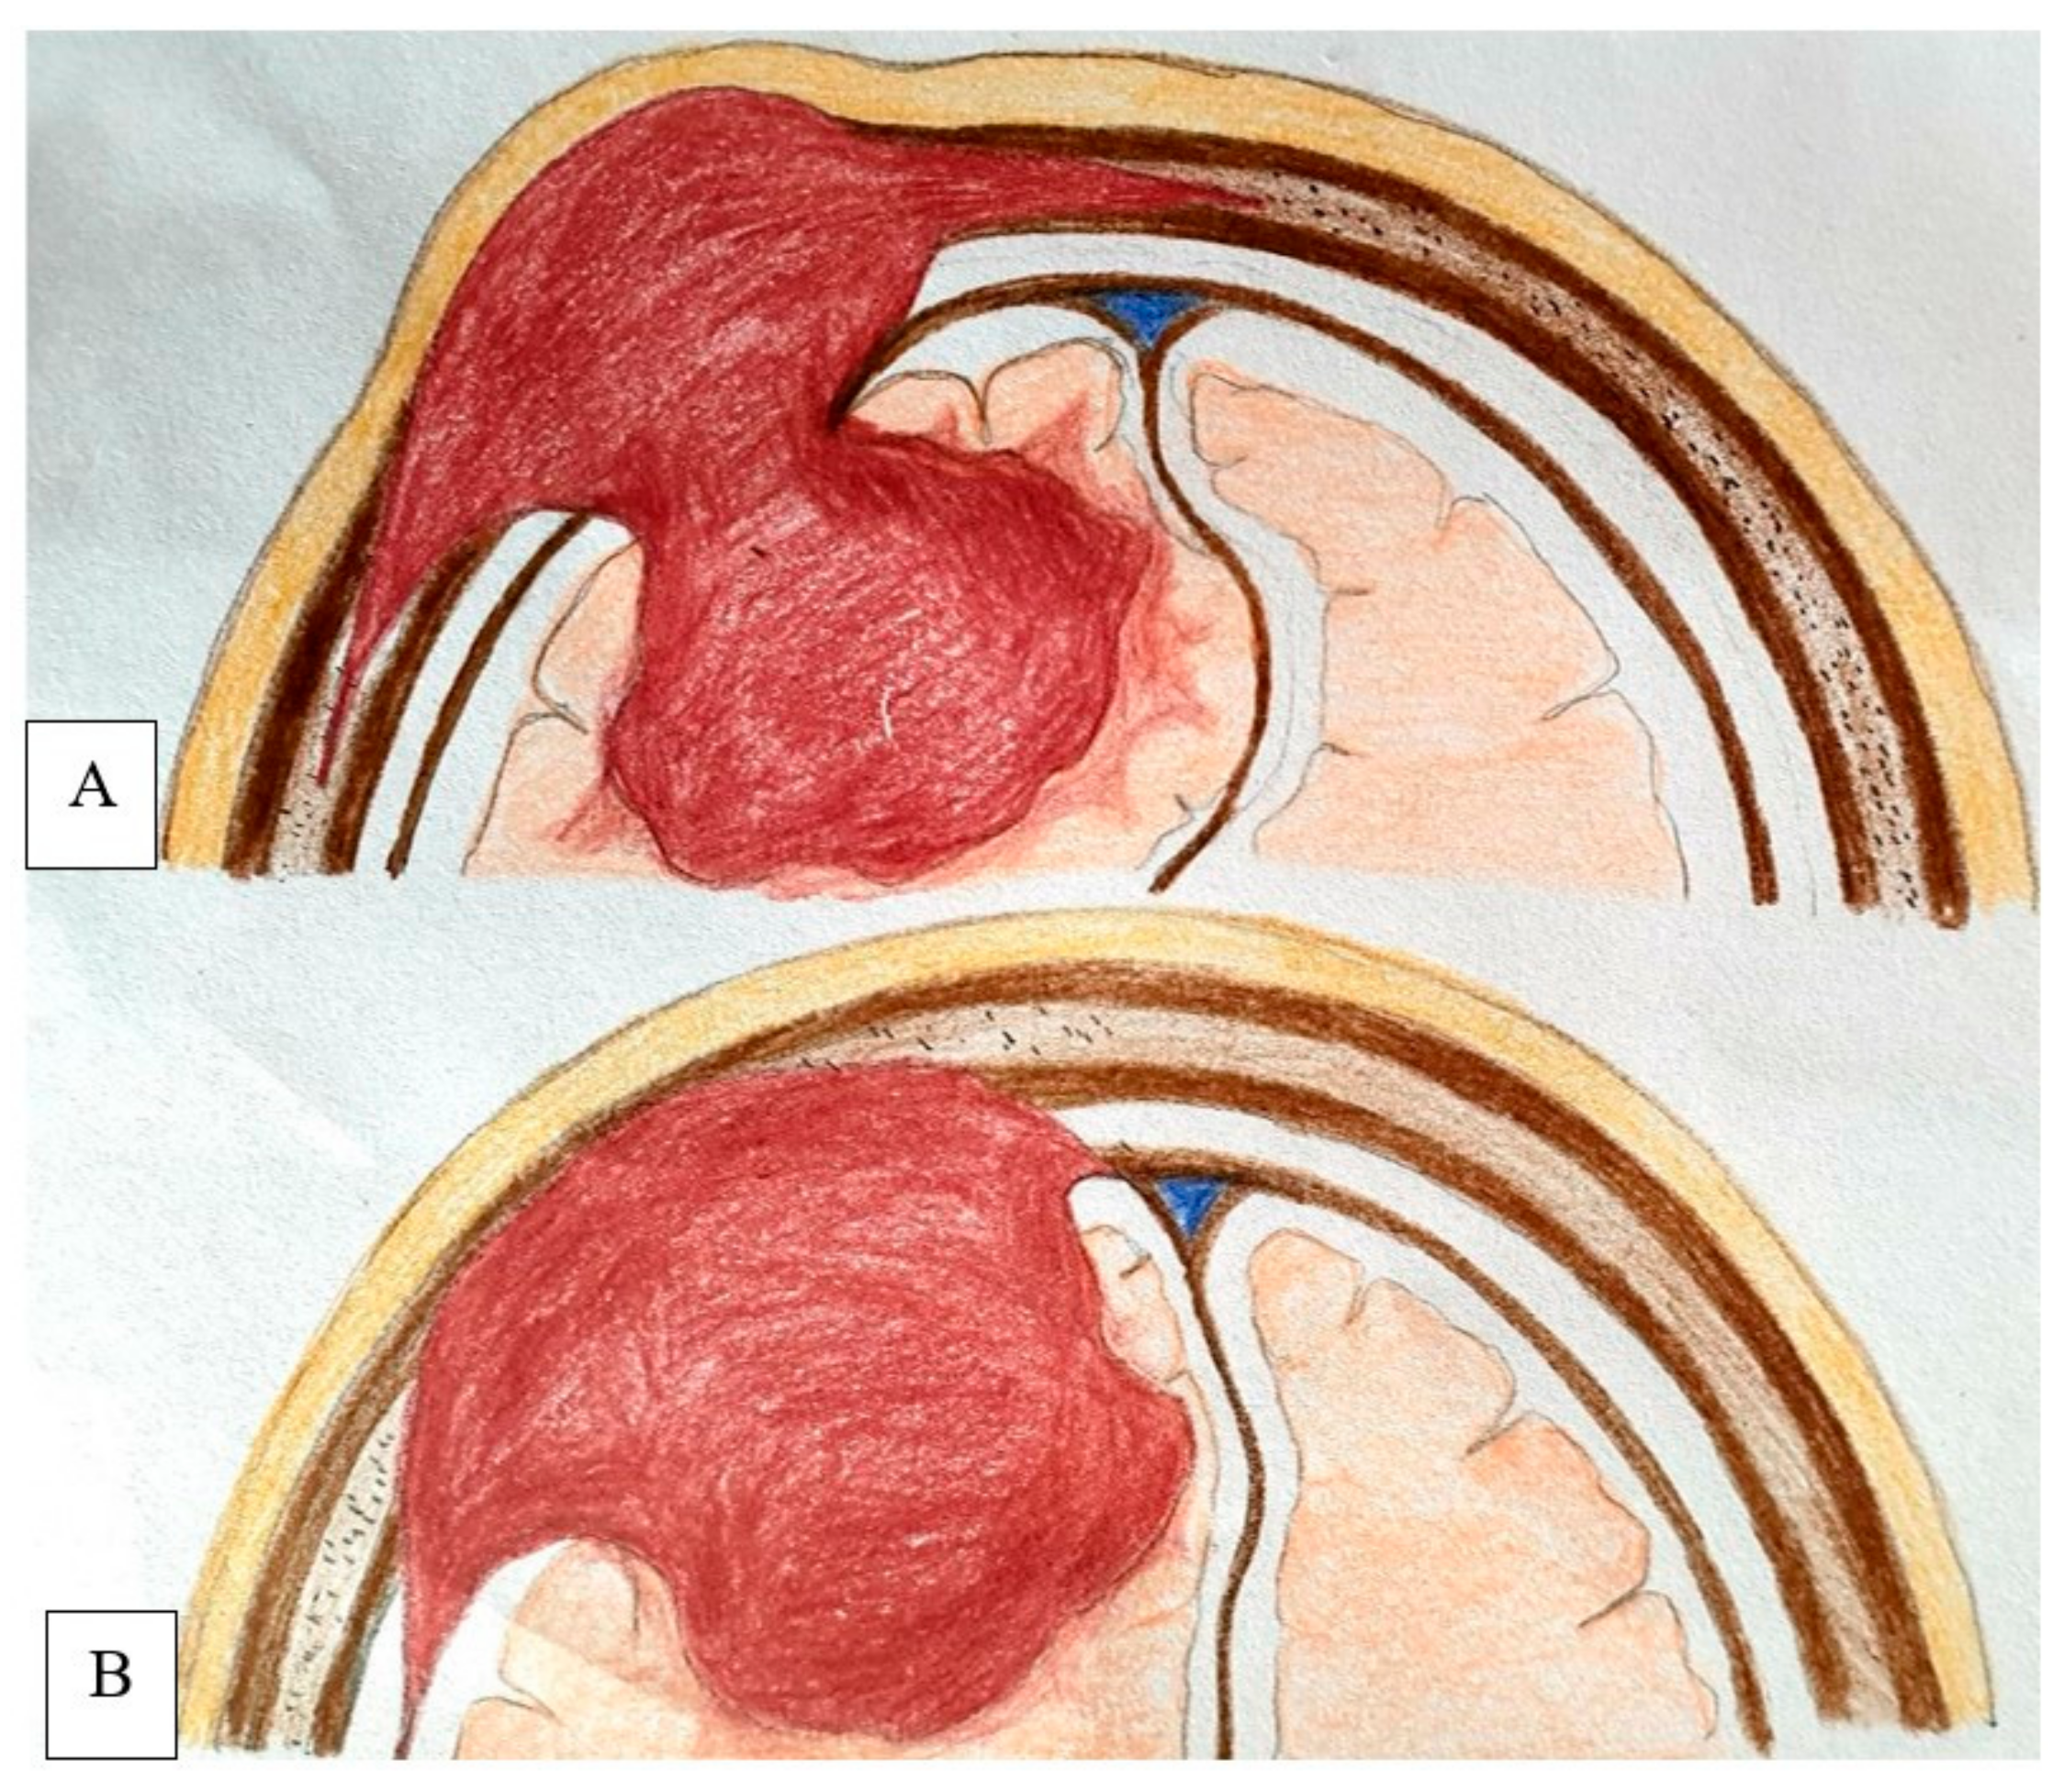

4.6. Extent of Dura and Soft Tissue Involvement

4.7. Recommended Management Strategy

4.9. Proposed New Classification